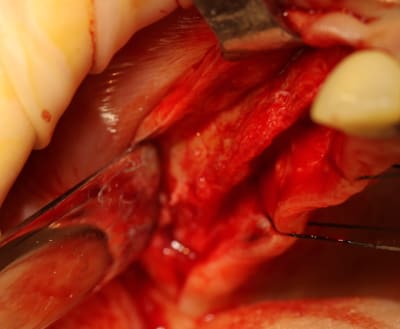

OK nous n'y sommes pas encore, mais je me suis fais une petite intervention sympa ce matin, avec un nouvel outil (qui n'est pas sur les photos ....because chut!) qui devrait permettre de simplifier la pratique de l'expansion, afin que tout un chacun puisse pratiquer ce sport sympa, et si tout va bien je pourrais vous en parler (peut être) en Juin.

ce n'est pas un cas simple, inversé d'occlusion, bruxo+++ haut et bas changé (6 à 8 fois)par plusieurs confrères (pas de critiques de ma part)et je tente de refaire l'ensemble, mais avec mes difficultés aussi.

pour 23 et suivant, si l'intervention se passe bien, le patient ne découvrant pas et la greffe en onlay n'ayant pas été retenue, ce sera une prothèse sur pilotis

Mais, ce post est surtout provoqué car j'ai utilisé un nouvel outil pour l'expansion et si la suite le confirme, les ostéotomes "classiques" pourraient bien êtres renvoyés sur l’étagère des outils du souvenir..